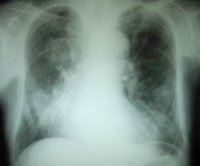

Bk94g.jpg

血常规尿常规粪常规等,心电图胸片超声心动图非常有意义,可以判断心功能损伤的程度。尤其是是超声心动图,可测量左室射血分数(LVEF),正常LVEF值>50%,LVEF≤40%为收缩期心力衰竭的诊断标准。一些实验室指标,比如心肌酶脑钠肽等对于心功能不全/心衰的判断也有意义。此外尚有放射性核素检查等多项检查。根据临床需要可以酌情考虑选取。心功能不全的辅助检查与心力衰竭是相同的,可以参考。